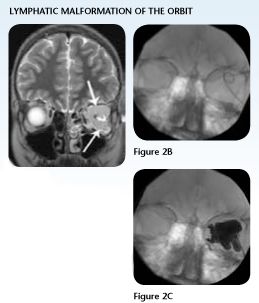

Case Study 2: Orbital Lymphatic Malformation

Jordan, age 13, dreamed of being able to do simple things that his friends enjoyed, such as running track, playing baseball and rollerblading, to name a few. Since the age of 3, Jordan had undergone treatment for a left orbital lymphatic malformation.

Each intervention provided little success at relieving his proptosis or recurrent symptoms. By age 13, when his lymphatic malformation flared up, it sent him to the hospital with a severe headache, visual loss and bradycardia.

Surgeons operated to attempt removal of the mass, drained the cystic spaces and consulted with experts around the country for other surgical options. One leading, east coast pediatric teaching center suggested that if additional treatment were attempted, they anticipated Jordan would have a three to four month inpatient stay, and the high risk of recurrence.

Before proceeding with additional surgical options, Jordan's oculoplastic surgeon in Kansas placed his case on the Internet, for fellow oculoplastic surgical opinions around the country. Dr. Kenneth Cahill, Oculoplastic Surgeon at Grant Medical Center and Nationwide Children's Hospital, read the e-mail and recommended that Jordan come to Nationwide Children's for treatment.

Following Dr. Cahill's recommendation, Jordan's surgeon followed up with his family, who opted to make the trip and bring their son to Nationwide Children's Hospital. Jordan needed just one interventional radiology procedure, with a 23-hour inpatient stay.

As a result of the procedure, Jordan no longer has proptosis and has no recurrence of his bradycardia. At age 13, Jordan is realizing his dream of enjoying the simple things. Now his biggest physical complaint is sore leg muscles from running track.